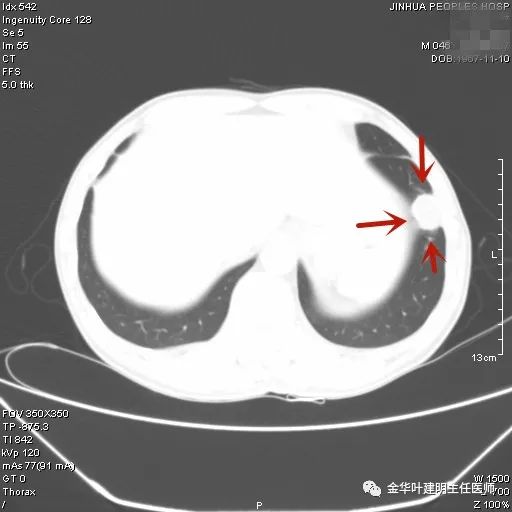

上图示鳞癌。病灶厚壁空洞,内壁凹凸不平,鳞癌可以乏收缩力,不一定有毛刺征或胸膜凹陷征。